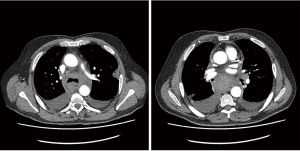

We describe a rare case of a postoperative mediastinal bleeding that occurred in our service related to coagulopathy disorder (Figures 1,2).

This 66-year-old man initially presented with haemoptysis and was found to have a left upper lobe lesion on computed tomography (CT). Positron emission tomography (PET) scan revealed a nodule with an SUVmax of 6.9 in the left upper lobe and hilar and paratracheal lymph nodes with SUVmax of 4.1 and 3.1 respectively, all suspicious for primary lung cancer. He was referred for mediastinoscopy for staging and diagnosis purposes. Past medical history included being an ex-smoker, myelofibrosis on medical treatment, chronic obstructive pulmonary disease (COPD), hypertension and gastro-oesophageal reflux. Preoperative haematological advice was to continue his medications. He underwent a cervical videomediastinoscopy, which was routine and uneventful. Stations 2R, 2L, 4R, 4L and 7 were sampled. There was minimal expected bleeding experienced when the biopsies were taken and haemostasis was achieved prior to closure. He was discharged home the same day.

Later that evening he re-presented with upper abdominal pain. Investigations revealed abnormal clotting with a slightly raised partial thromboplastin time (PTT) and activated partial thromboplastin time (aPTT), a raised white cell count and haemoglobin that had decreased by 10 g/L from pre-operatively. Chest X-ray showed a slightly widened mediastinum. A CT scan showed a mediastinal haematoma predominantly in the subcarinal region, extending inferiorly to the oesophageal hiatus and superiorly around the carina and distal trachea, along with bilateral pleural effusions, right larger than left. Aortic and bronchial angiogram did not demonstrate a bleeding point, and also found that anyway the bronchial arteries were very small and not easily amenable to embolization. Haematological advice this time supported the impression of coagulopathy due to myelofibrosis, replacement of coagulation factors was prescribed.

Due to the concern of persistent small bleeding the patient underwent a right VATS drainage of haemothorax and exploration of the mediastinum. The mediastinal pleura was opened fully and drained but no specific bleeding point could be identified. The subcarinal region was explored round to the origin of the left main bronchus where there was possibly a bleeding point from the bronchial artery. Haemostasis was achieved and the chest washed out with saline and 3 g tranexamic acid. He then underwent a left VATS evacuation of haemothorax, the subcarinal region was explored and no active bleeding point was identified from the left bronchial artery. He finally made a steady recovery and was eventually safely discharged.